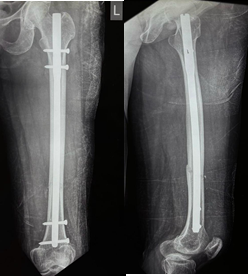

Figure 3: Anteroposterior and lateral views at 3 months showing distal third fracture of femur with retrograde nail.

Out of all study participants, 58 patients had closed fractures and rest 2 patients had compound fractures. The mean operation-injury interval was 5.5 ± 0.67 days for antegrade nailing and 5.8 ± 0.65 days for retrograde nailing. The mean duration of the surgery was 85 ± 2.15 min for retrograde nailing and 95 ± 1.39 min for antegrade nailing. Mean time for radiological union with retrograde nailing was 10 ± 0.38 weeks (Fig. 1, 2, 3, 4) and with antegrade nailing, it was 14 0.44 weeks (Fig. 5, 6).

The mean post-operative knee ROM achieved with retrograde nailing was 117.3 ±2° and with antegrade nailing, it was 114.4 ± 1.8°. Mean time for partial weight bearing was 9.27 ± 0.37 weeks with retrograde nailing, an 10.9 ± 0.49 weeks in antegrade nailing. Mean time for full weight bearing was 15 ± 0.47 weeks in retrograde nailing and 18.2 ± 0.67 weeks in antegrade nailing (Tables 3, 4, 5).